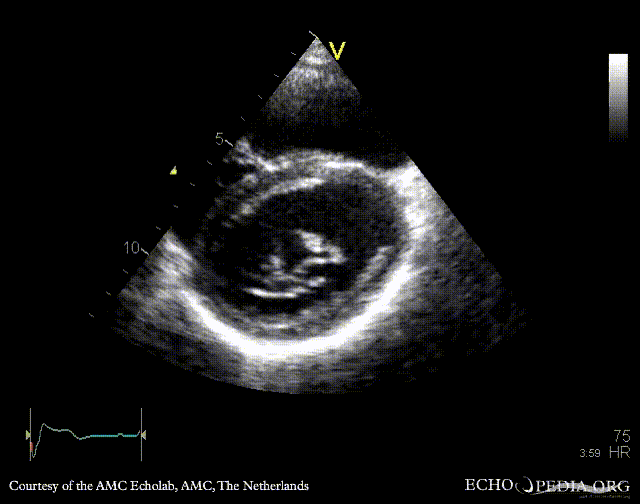

PSAX: cleft of mitral valve